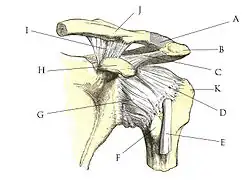

A : ligament acromio-claviculaire. B : acromion. C : ligament coraco-acromial. D : ligament coraco-huméral. E : tendon du long chef du biceps. F : tubercule mineur de l'humérus, ou trochin. G : capsule ligamentaire. H : processus coracoïde. I : ligament coraco-claviculaire (comportant le trapézoïde et conoïde). J : clavicule. K : tubercule majeur, ou trochiter

Le complexe articulaire de l'épaule met en relation quatre os :

- le manubrium sternal (ainsi que le premier cartilage costal) ;

- la clavicule ;

- l'omoplate (scapula) ;

- la tête humérale.

Moyens de renforcements :

- bourrelet glénoïdal : c'est un anneau fibro-cartilagineux qui repose sur le bord de la cavité glénoïdale. Il permet ainsi d’en augmenter la surface et la profondeur. Son sommet est libre, sa face périphérique répond à la capsule ; sa face interne répond à la face articulaire de l'humérus ;

- deux tendons, le long biceps et le long triceps .

La capsule articulaire est un manchon fibreux très lâche. Son insertion se fait sur le col de l’humérus et sur la cavité glénoïdale ; elle est renforcée par deux ligaments : un passif et un actif.

Le passif : c’est en fait une individualisation de la capsule articulaire (fragment supérieur), il est constitué de deux ligaments :

- Coracohuméral → deux faisceaux partant du processus coracoïde vers les tubercules majeur (trochiter) et mineur (trochin).

- Glénohuméral → trois faisceaux :

- Supérieur : dans la partie antérieure supérieure de la capsule vers le bas, le dehors et le tubercule mineur.

- Moyen : dans la partie antérieure supérieure de la capsule vers le dehors, le bas et le tubercule mineur.

- Inférieur : dans la partie antérieure inférieure, vers le tubercule mineur ; c’est le plus puissant des trois ligaments.

Entre les ligaments glénohuméraux supérieur et moyen se trouve une zone de faiblesse, c’est le foramen ovale (foramen de Weitbrecht) ; il est simplement recouvert par le tendon du muscle subscapulaire. Il y a un autre point de faiblesse entre les ligaments inférieur et moyen, le foramen triangulaire (foramen de Rouvière) : c’est la zone de luxation antérieure de l’humérus.